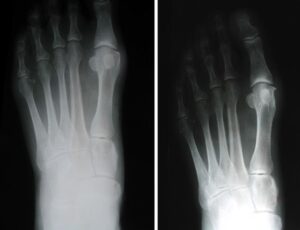

In this procedure, which is also called a fusion, your doctor removes the arthritic joint surfaces, then inserts screws, wires, or plates to hold the surfaces together until the bones heal.Arthrodesis is commonly used for patients who have severe bunions and/or severe arthritis, and for patients who have had previous unsuccessful bunion surgery.

In this procedure, your doctor removes the bump from your toe joint. Exostectomy alone is rarely used to treat bunions because it does not realign the joint. Even when combined with soft tissue procedures, exostectomy rarely corrects the cause of the bunion.Exostectomy is most often performed as one part of an entire corrective surgery that includes osteotomy, as well as soft-tissue procedures. If a doctor performs exostectomy without osteotomy, however, the bunion deformity often returns.

Because bunions vary in shape and size, there are different surgical procedures performed to correct them. In most cases, bunion surgery includes correcting the alignment of the bone by cutting and shifting the bones. This will most likely require the placement of surgical hardware (plates and screws) as well as repairing the soft tissues around the big toe. Your doctor will talk with you about the type of surgery that will best correct your bunion.

An osteotomy is a surgical procedure in which your doctor makes precise cuts in the bones to realign the joint and correct the bunion deformity. After cutting the bone, the newly adjusted position is stabilized using pins, screws, or plates. This realignment ensures the bones are straighter and the joint is properly balanced.How Osteotomy Works

You may require several preoperative tests, including blood counts, an echocardiogram, and a chest X-ray. You may also need to provide a urine sample.To help plan your procedure, your doctor may order special foot X-rays. These X-rays should be taken in a standing, weightbearing position to ensure your doctor can clearly see the deformity in the foot. These special X-rays assist your doctor in making decisions about where along the bone to perform an osteotomy to provide enough corrective power to straighten the toe.